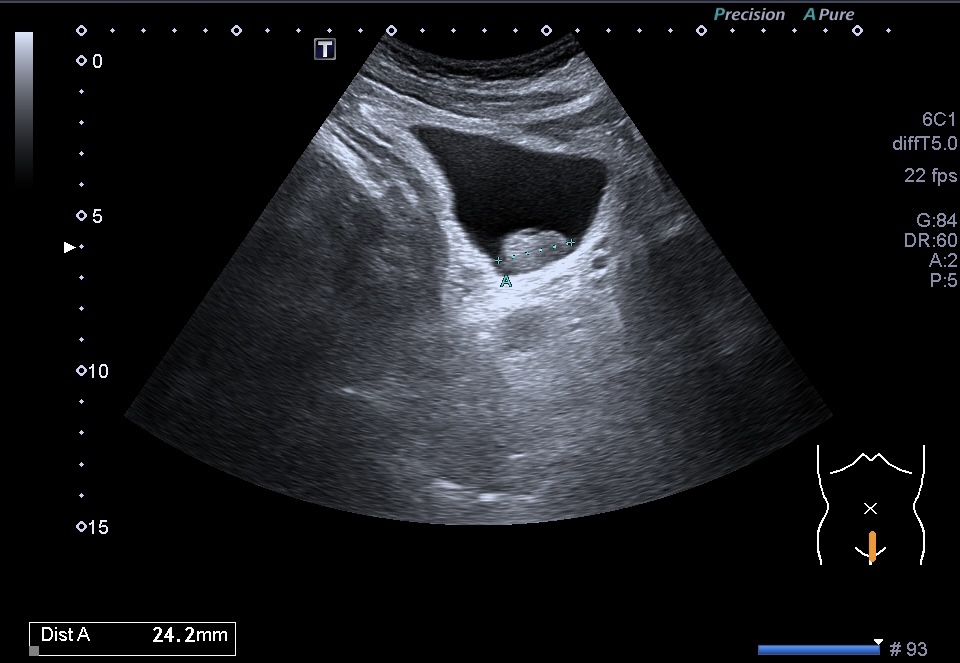

Al realizar una ecografía reno vesical, los hallazgos ecográficos típicos del urotelioma incluyen la visualización de una masa sólida en la vejiga.

Esta masa puede presentar una apariencia heterogénea, con áreas hipoecoicas (menos ecogénicas) y áreas hiperecoicas (más ecogénicas) en relación con el tejido circundante. Además, puede observarse un crecimiento intraluminal, lo que significa que la masa se proyecta hacia el interior de la vejiga.

- Contornos: Los contornos de la masa pueden ser irregulares y asimétricos. Pueden observarse proyecciones intraluminales, lo que indica que la masa se extiende hacia el interior de la vejiga.

- Tamaño: El tamaño de un urotelioma puede variar desde pequeñas lesiones hasta masas más grandes que ocupan una parte significativa de la vejiga.

- Estructura interna: La estructura interna del urotelioma puede ser heterogénea debido a la presencia de áreas de necrosis o hemorragia. Estas áreas pueden ser identificadas por su apariencia hipoecoica o hiperecoica respectivamente.También calcificiones…como es el caso que nos ocupa hoy.